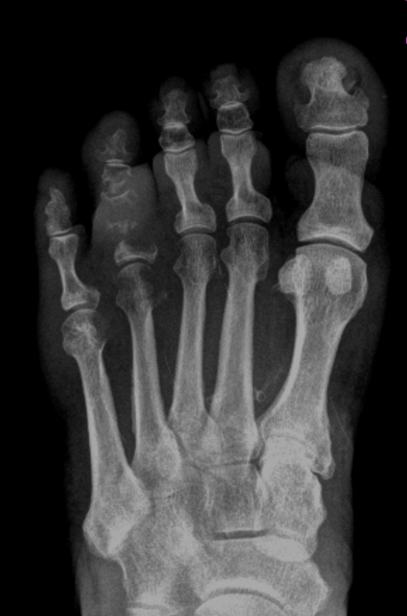

Radiografias

Radiografia é um exame que avalia a conformidade óssea. Sabemos que para vermos uma alteração real no RX é necessária uma destruição óssea de aproximadamente 30% do osso. Assim, como a velocidade de destruição óssea das bactérias usualmente são lentas, a osteomielite aguda não é possível de ser identificada em radiografias, pois nesta fase ainda não há destruição óssea, apenas inflamação. Portanto, as radiografias conseguem dar o diagnóstico apenas da osteomielite crônica,